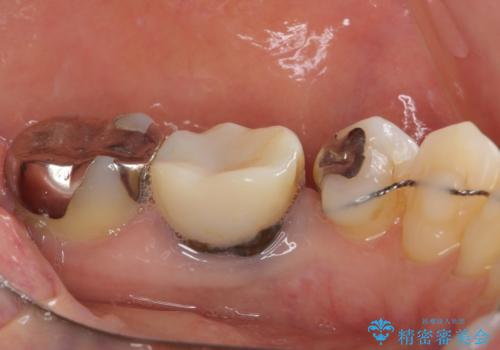

- 矯正治療を行った歯科医院で装着した前歯の仮歯が不快とのことで来院された患者様です。

仮歯自体はとても綺麗でしたが、2本の歯が欠損している部分に上唇小帯が入り込んでいたため、歯肉形成を行った上で仮歯を調整し、オールセラミックブリッジを装着することとしました。

他にも治療が必要な歯があったため、合わせてセラミッククラウンやセラミックインレーで治療することとしました。